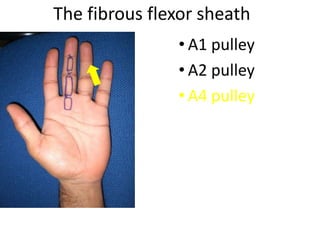

- It describes flexor tendon zones, extensor compartments, and pulley system anatomy.